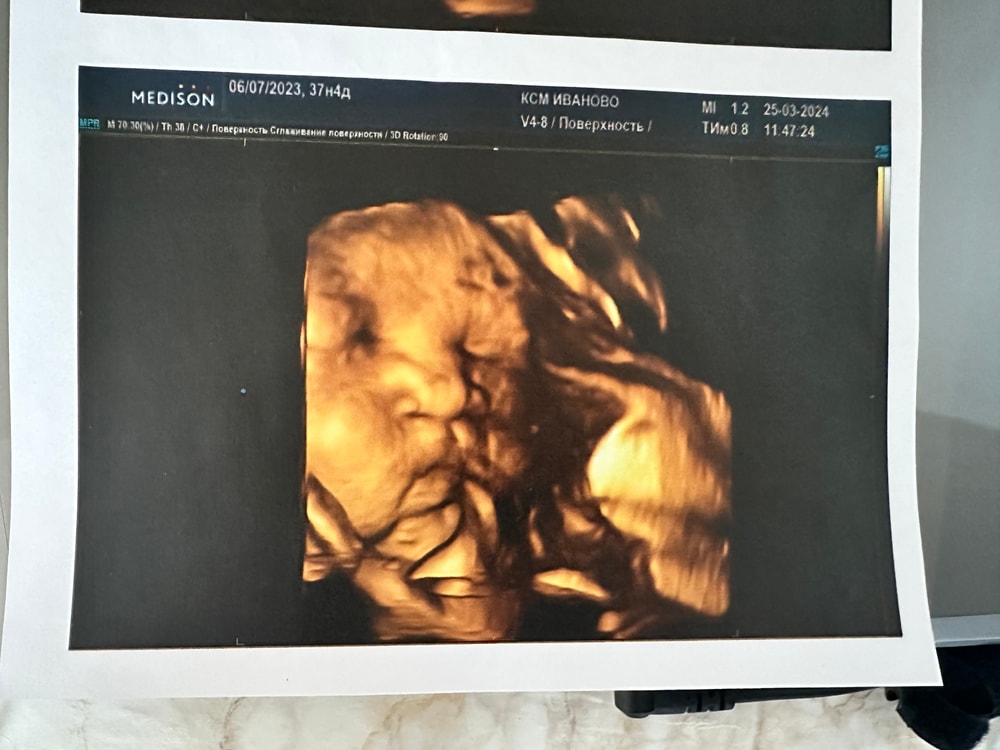

Видно будет если ребёнок захочет показать, я так скажу 😂 У меня на 22 неделе очень хорошо было видно черты лица ребёнка) в 32 - ещё лучше) там даже узистка сказала, что на папу похож) Изображение Изображение